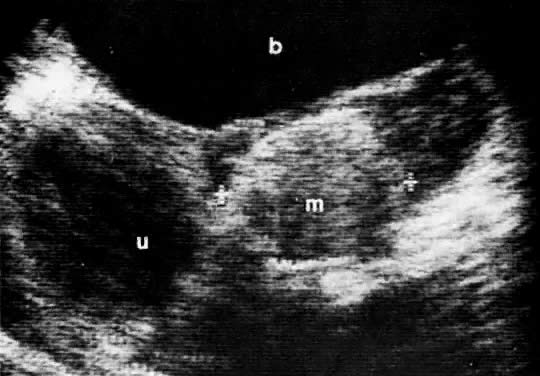

In locally confined disease, a cervical mass may be seen by ultrasound (Fig. 5B and C). In locally advanced disease, the cervix may become diffusely enlarged, inhomogeneous, and irregularly marginated (Fig. 6A and B).

The presence of hydrometras should raise the suspicion of cervical or endometrial carcinoma. It is best demonstrated by ultrasound (see Fig. 6A), but can be seen by both MRI (Fig. 7) and CT (Fig. 8).11,12 This finding, however, is nonspecific because it can also be seen in benign cervical strictures caused by either previous cervical inflammation (Fig. 9) or pelvic irradiation (Fig. 10).

Fig. 9. Sagittal scan of the uterus ( u) shows hydrometras. Cervix ( c) is normal in size. Patient had no known cervical or endometrial cancer.

Ultrasound may play a role in the evaluation of tumor extension to the parametrium and the pelvic sidewall in patients with an equivocal pelvic examination.38,39 In stage IB, the tumor is confined to the cervix on ultrasound, without parametrial extension (see Fig. 5B and C). In stage IIB, a tongue of the hypoechoic soft-tissue mass extends laterally from the cervix (see Fig. 6B). More recently, high-resolution transrectal ultrasound was found to be more sensitive in assessing parametrial tumor spread compared to clinical evaluation (78% vs 52%, respectively).40 Ultrasound is also capable of detecting tumor extension into the bladder (Fig. 20),39,41 hydronephrosis (Fig. 6C),38 and/or ureteral obstruction (see Fig. 6B). Unlike CT, however, it cannot always reliably evaluate the level and cause of the obstruction.